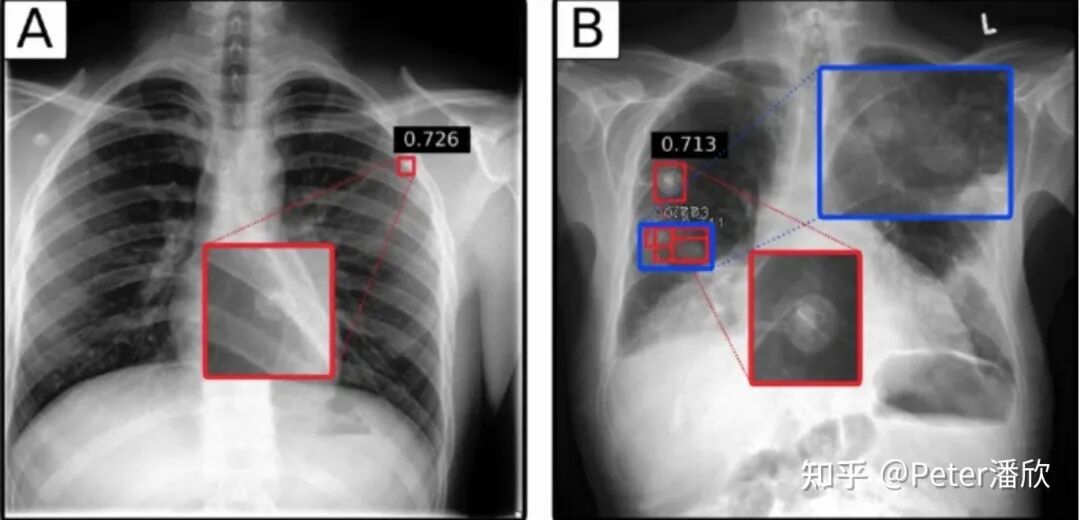

8.3 医疗影像的应用

17年Brain下成立一个放射科的医疗影像团队:Radiology。由于我正好在这个领域开发模型,就帮助了这个团队的创建。 最初我们先从简单的XRay下手。我将FasterRCNN先经过CoCo的预训练,然后再几百张XRay样本上做了一些fine-tune,结果意外的好。 后来我们深入到更难的CT场景。CT是对人进行3维立体的扫描,因此对应的框需要包含长宽高。由于当时是兼岗,我简单将CT做了抽帧,转换成多张二维图片,然后通过FasterRCNN,然后再三维化。这样效果比较一般。后来一个韩国小哥实现了一个高性能的3D检测,取得了更好的效果。 花絮 AI医疗的上线是非常困难的,特别是在美国这种FDA管理比较严格的国家。当时我们找到一个场景,据说是不需要FDA Apporve的: 通常需要被诊断的Radiology数据是FIFO排队被医生诊断的。这就有个问题,有可能某个人的情况很紧急(比如车祸胸部骨折),但是他的XRay被排在了后面,耽误了诊断。我们可以用AI模型对这些XRAY做一个严重程度的排序,给医生提出建议。另外,我们还在印度搞了流动医疗车,免费提供相关的诊断。